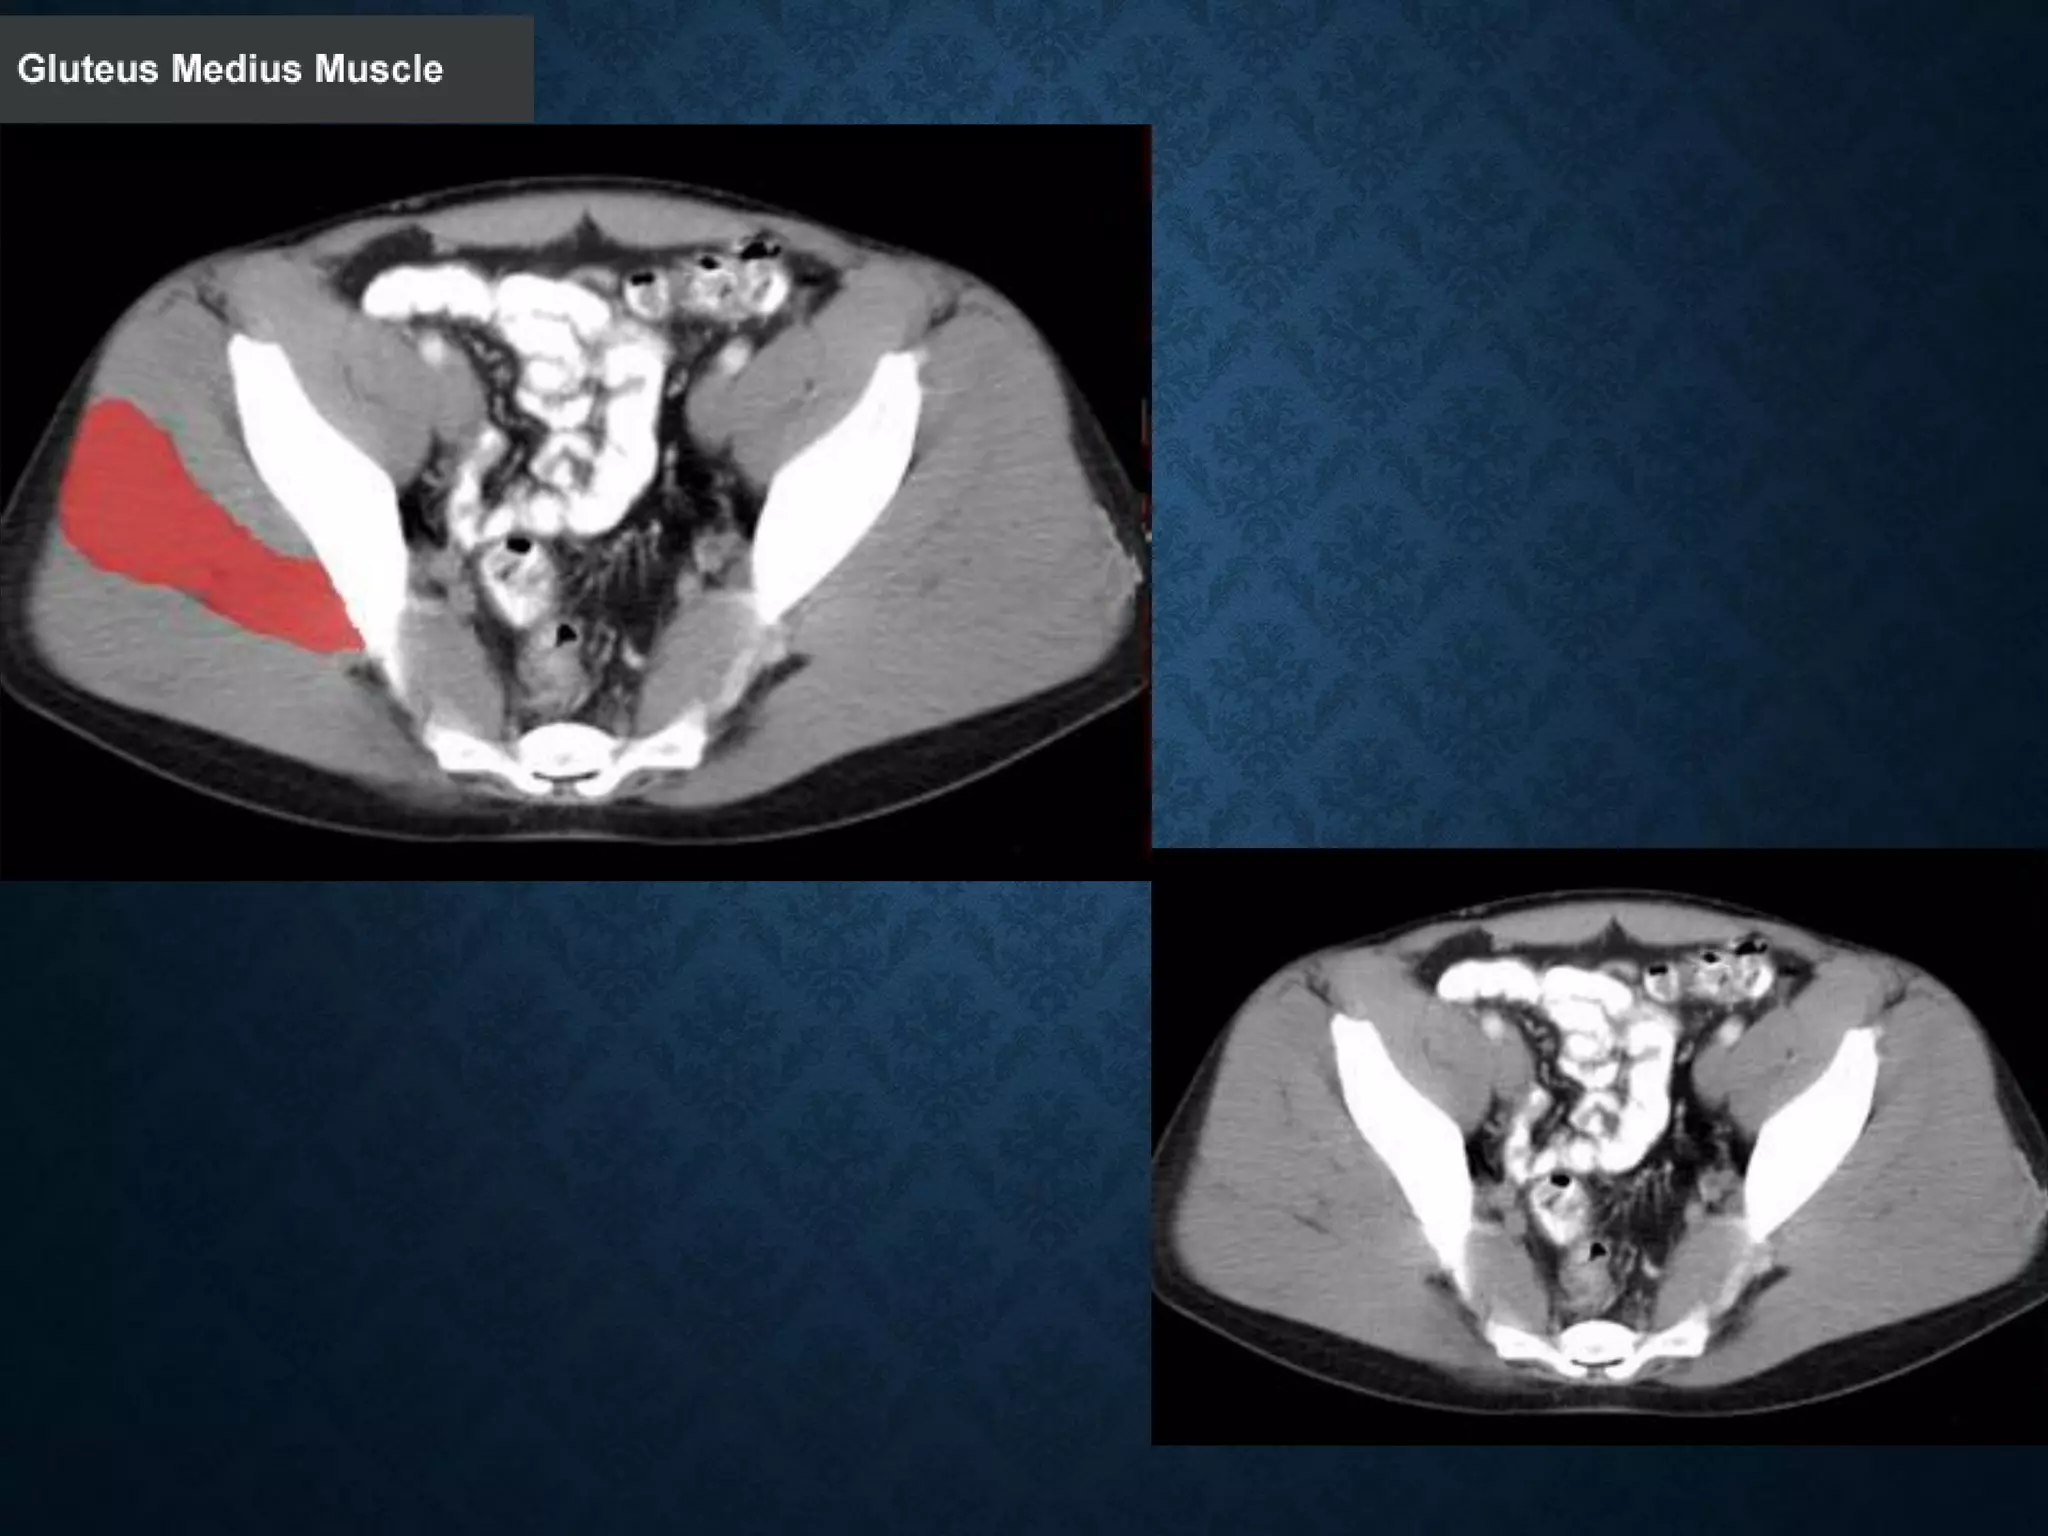

Identify the following structures in the body CT to the right. To view the location of the structure in the image click on

the label at the left and the structure will be indicated in the image. Abdominal CT scans typically begin just above

the diaphragm, so the first slice you see is of the lower chest.